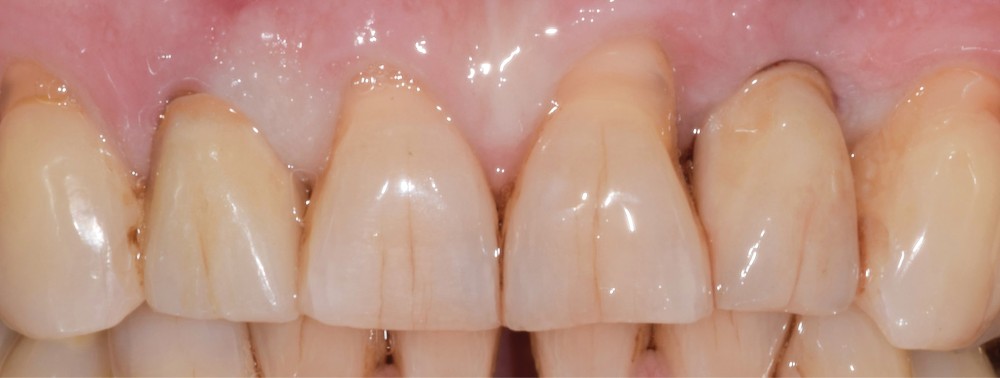

Situation initiale

Un patient de 62 ans se présente en consultation afin de réaliser les coiffes prothétiques des dents 12 et 22. La 12 présente une restauration par prothèse transitoire non adaptée. Un implant au niveau de la 22 a été posé par un autre praticien selon une technique chirurgicale en deux temps. Le praticien a adressé le patient pour la réalisation prothétique. L’option de bridge collé cantilever mono ailette n’avait pas été retenue ou proposée selon une technique chirurgicale en deux temps. Le patient souhaite rétablir l’esthétique et la fonction de ces deux dents uniquement.